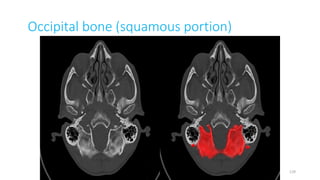

Occipital bone (squamous part)

Occipital bone (squamous portion)

Occipital bone, squamous part

SQUOMOS OCCIPUT

SQUAMO OCCIPUT

SQUAMOUS OCCIPITO

SQUAMO- OCCIPITO